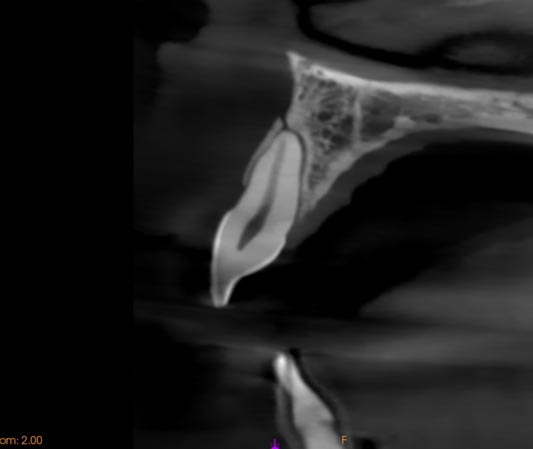

El uso del CBCT permite valorar con mayor precisión la extensión de la reabsorción y definir mejor el abordaje terapéutico.

Imágenes:

Imagen de CBCT mostrando el alcance de una Reabsorción Cervical Invasiva.

Caso resuelto mediante endodoncia y tratamiento quirúrgico.

Imágenes: Imagen de CBCT que muestra una fractura ósea de un paciente tras haber sufrido un trauma dental.